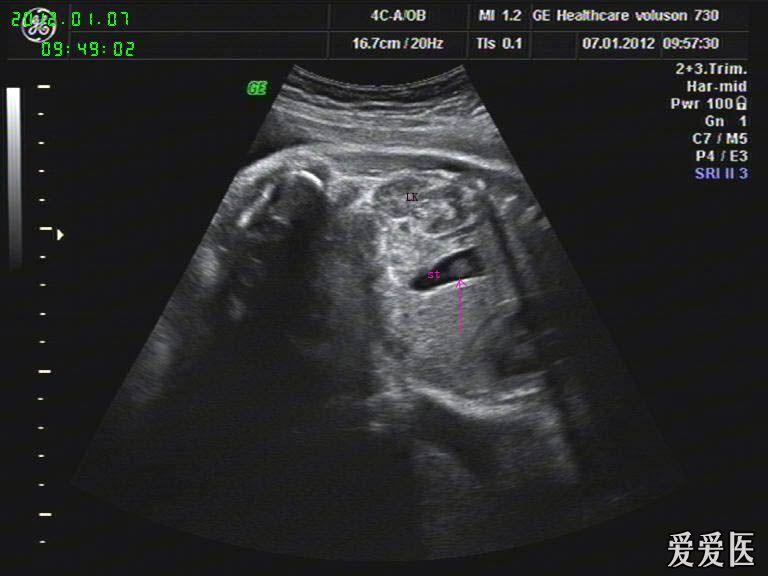

图一 镜面右位心 心尖和胃泡位于右侧

a示左膈肌 明显抬高,胃泡 上移.

孕23周胃泡是多少

胎儿胃泡内低回声团块